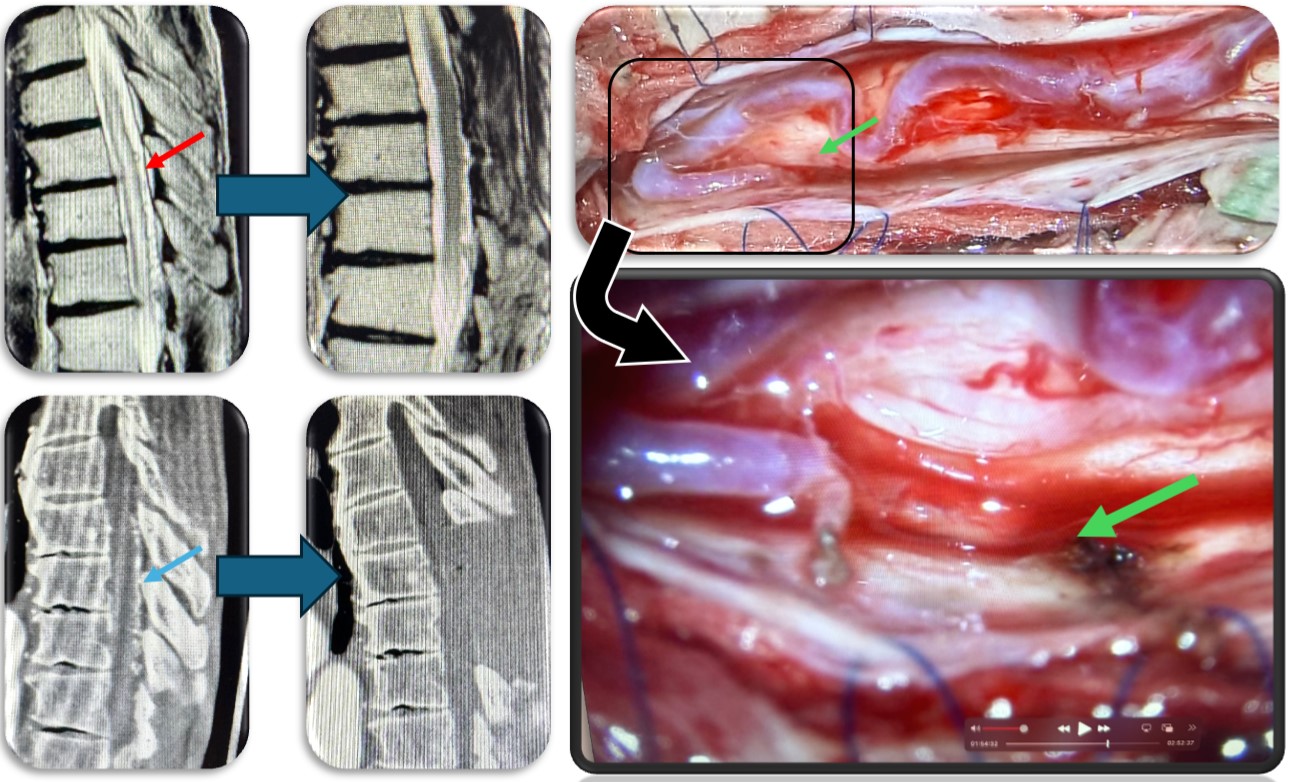

(代表例)

腰部の馬尾神経に発生した神経鞘腫の症例。脊髄腫瘍としては比較的多く割合を占める神経鞘腫は良性腫瘍であり、基本的には全摘出が可能で予後も良好です。この症例も坐骨神経痛と間欠跛行という馬尾障害の症状を呈していましたが、術後は改善し再発も認めておりません。

(代表例①)

硬膜動静脈瘻の症例です。脊髄血管奇形の中では最も多い疾患です。脊髄の静脈に動脈血流が直接流入する事により脊髄浮腫をきたし(赤矢印)、様々な神経症状が出ます。最近では血管内から治療することもありますが根治率は20%程度と非常に低く、基本的には高い確率で根治できる外科的治療を施します。当院では基本的には外科的治療を選択しますが、高齢者や外科的治療が困難な症例では血管内治療を検討することもあります。手術では動脈から静脈に直接流入する部位(緑矢印)を焼灼離断します。術直後に脊髄浮腫は改善し、造影CT検査で描出の認めた異常血管影(青矢印)は術後に消失しました。